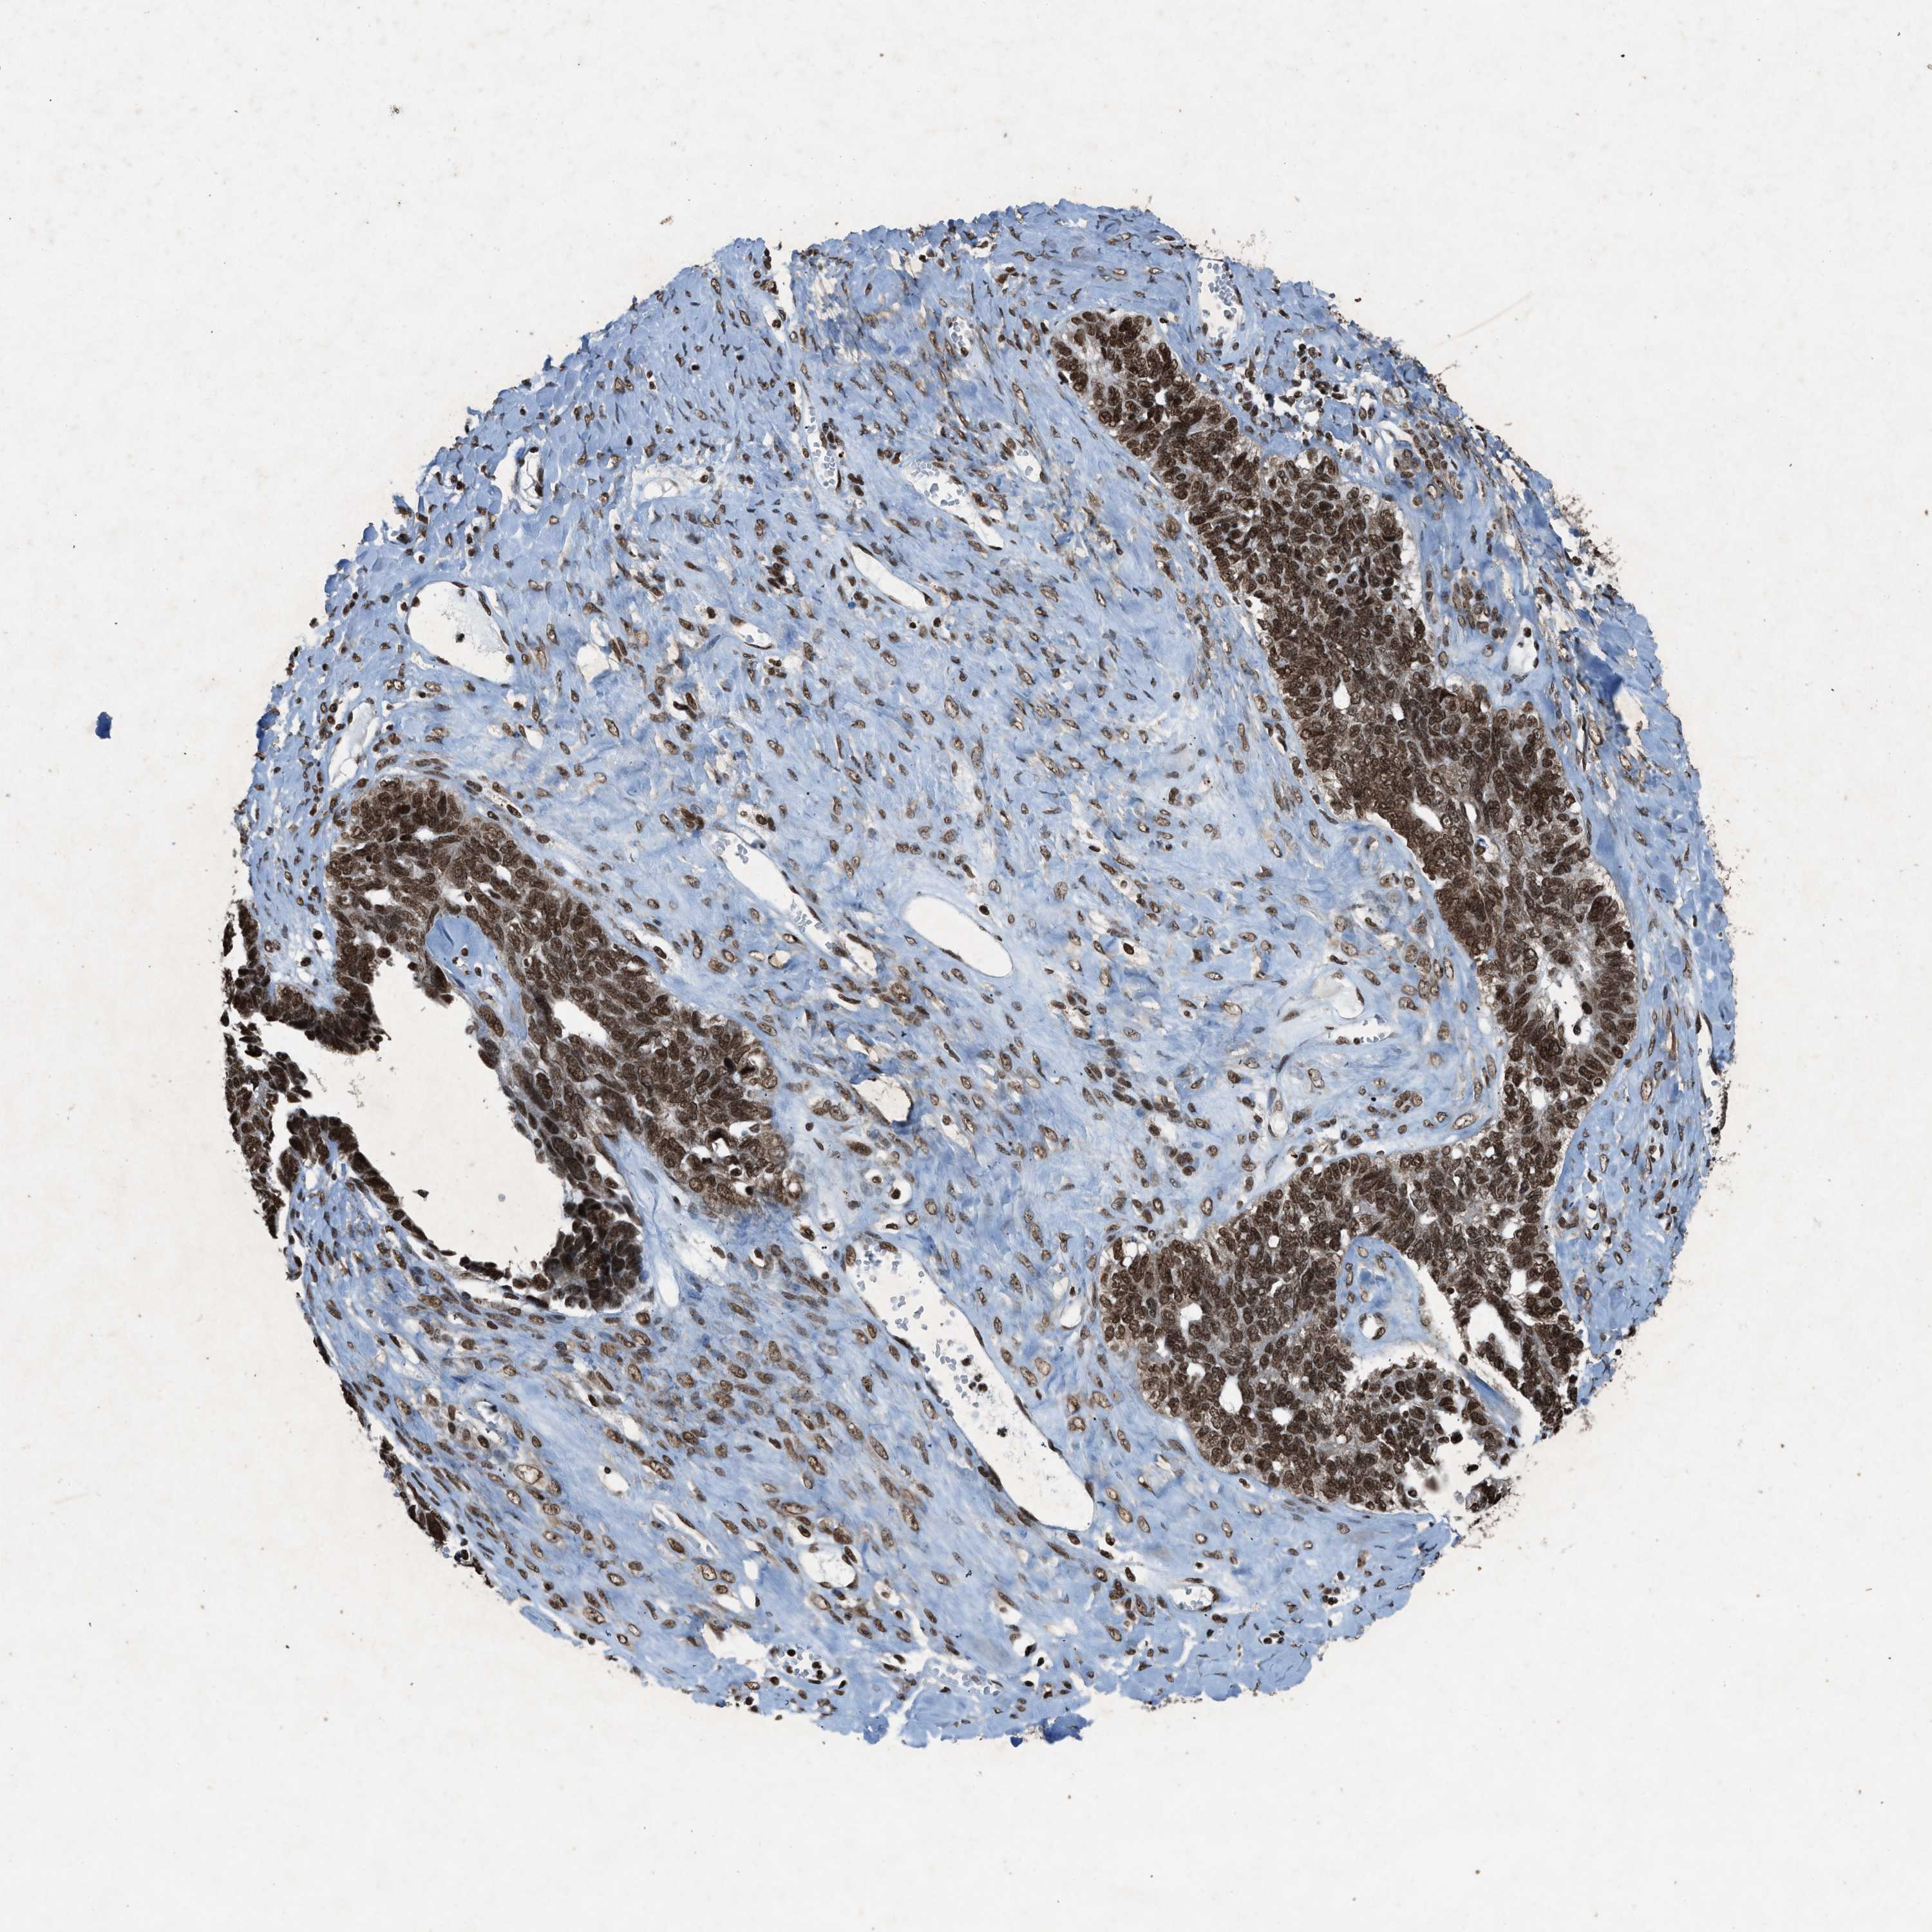

OVARIAN CANCER - Protein expressioni

A mouse-over function shows sample information and annotation data. Click on an image to view it in a full screen mode. Samples can be filtered based on level of antibody staining by selecting one or several of the following categories: high, medium, low and not detected. The assay and annotation is described here.

Note that samples used for immunohistochemistry by the Human Protein Atlas do not correspond to samples in the TCGA dataset.

Antibody stainingi

Antibody staining in the annotated cell types in the current human tissue is reported as not detected, low, medium, or high, based on conventional immunohistochemistry profiling in selected tissues. This score is based on the combination of the staining intensity and fraction of stained cells.

Each image is clickable and will lead to virtual microscopy that enables deeper exploration of all samples and also displays staining intensity scores, fraction scores and subcellular localization as well as patient and tissue information for each sample.

Antibody HPA061593

Antibody CAB016327

Staining

High

Medium

Low

Not detected

Intensity

Strong

Moderate

Weak

Negative

Quantity

>75%

75%-25%

<25%

None

Location

Nuclear

Cytoplasmic/membranous

Cytoplasmic/membranous,nuclear

Cystadenocarcinoma, serous, NOS

Cystadenocarcinoma, mucinous, NOS

Carcinoma, endometroid

Carcinoma, NOS